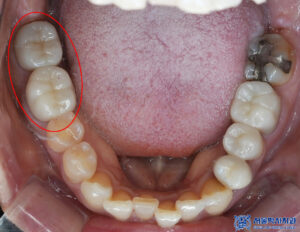

해당 환자분의 경우,

기존 보철물이 있던 부위에서

우식이 많이 발견되었습니다.

그래서 신흥동치과 서울박사에서는

우선적으로 자연치아를 살릴 수 있는 가능성을

그냥 지나치지 않으려고 노력하기에

살릴 수 있는 치아는 크라운을

새로 제작하여 자연치아를 살리려고 노력합니다.

그래서 내부의 충치를 깨끗하게 제거한 후

치아를 다듬어 보철 작업을 진행하였습니다.

또한 오른쪽 아래 부위 역시

기존 보철물을 제거한 뒤

남은 치아를 깨끗하게 정리하고,

형태를 다듬어 보철 치료를

다시 진행하였습니다.